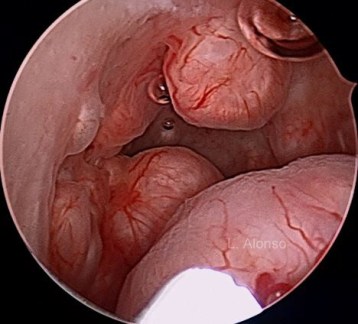

Los miomas o fibromas son tumores monoclonales benignos del útero, compuestos principalmente de células de músculo liso y de una matriz extracelular. Son los tumores sólidos más frecuentes de la pelvis femenina y su prevalencia varía ampliamente dependiendo de la edad, la raza y los antecedentes familiares, pudiendo encontrarse en más del 50% de las mujeres de 50 años.

Los miomas que distorsionan la cavidad se asocian a menores tasas de embarazo clínico, implantación y recién nacido vivo, así como a un incremento en las tasas de aborto espontáneo. No sucede lo mismo con aquellos miomas que no afectan a la cavidad uterina.

Cuando se precisa de cirugía para quitar los miomas, el abordaje mínimamente invasivo debe ser elegido, ya que es además la opción más segura para la paciente.

Antes de considerar una miomectomía deben tenerse en cuenta el tamaño del mioma, número de miomas, localización del mismo, la existencia de alguna enfermedad pélvica coexistente y sobre todo la experiencia quirúrgica del cirujano, es el factor más importante para mantener un útero en las mejores condiciones para llevar adelante el embarazo.